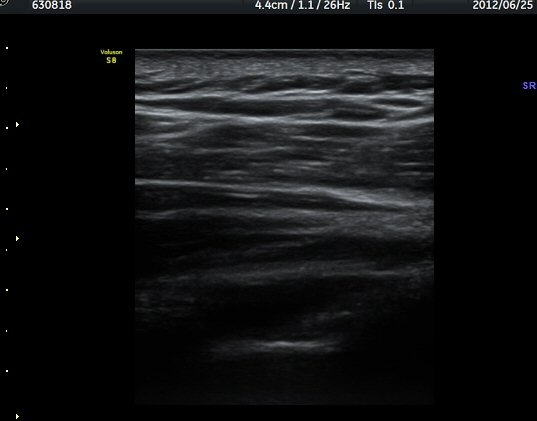

ÁÖ»ç¹Ù´Ã ÈíÀÎ(µ¿¿µ»ó Âü°í) 4ÀÏ ÈÄ °üÂûÇÑ ¼Ò°ß¿¡¼­´Â ³¶Á¾ÀÇ Å©±â °¨¼Ò°¡ ¶Ñ·ÈÇÏÁö ¾Ê´Ù(±×¸² 5, 6).

ÈíÀÎ 14ÀÏ ÈÄ ÃÊÀ½ÆÄ°Ë»ç¿¡¼­ ¾à°£ÀÇ ³¶Á¾ Å©±â °¨¼Ò°¡ °üÂûµÈ´Ù(±×¸² 7, 8)